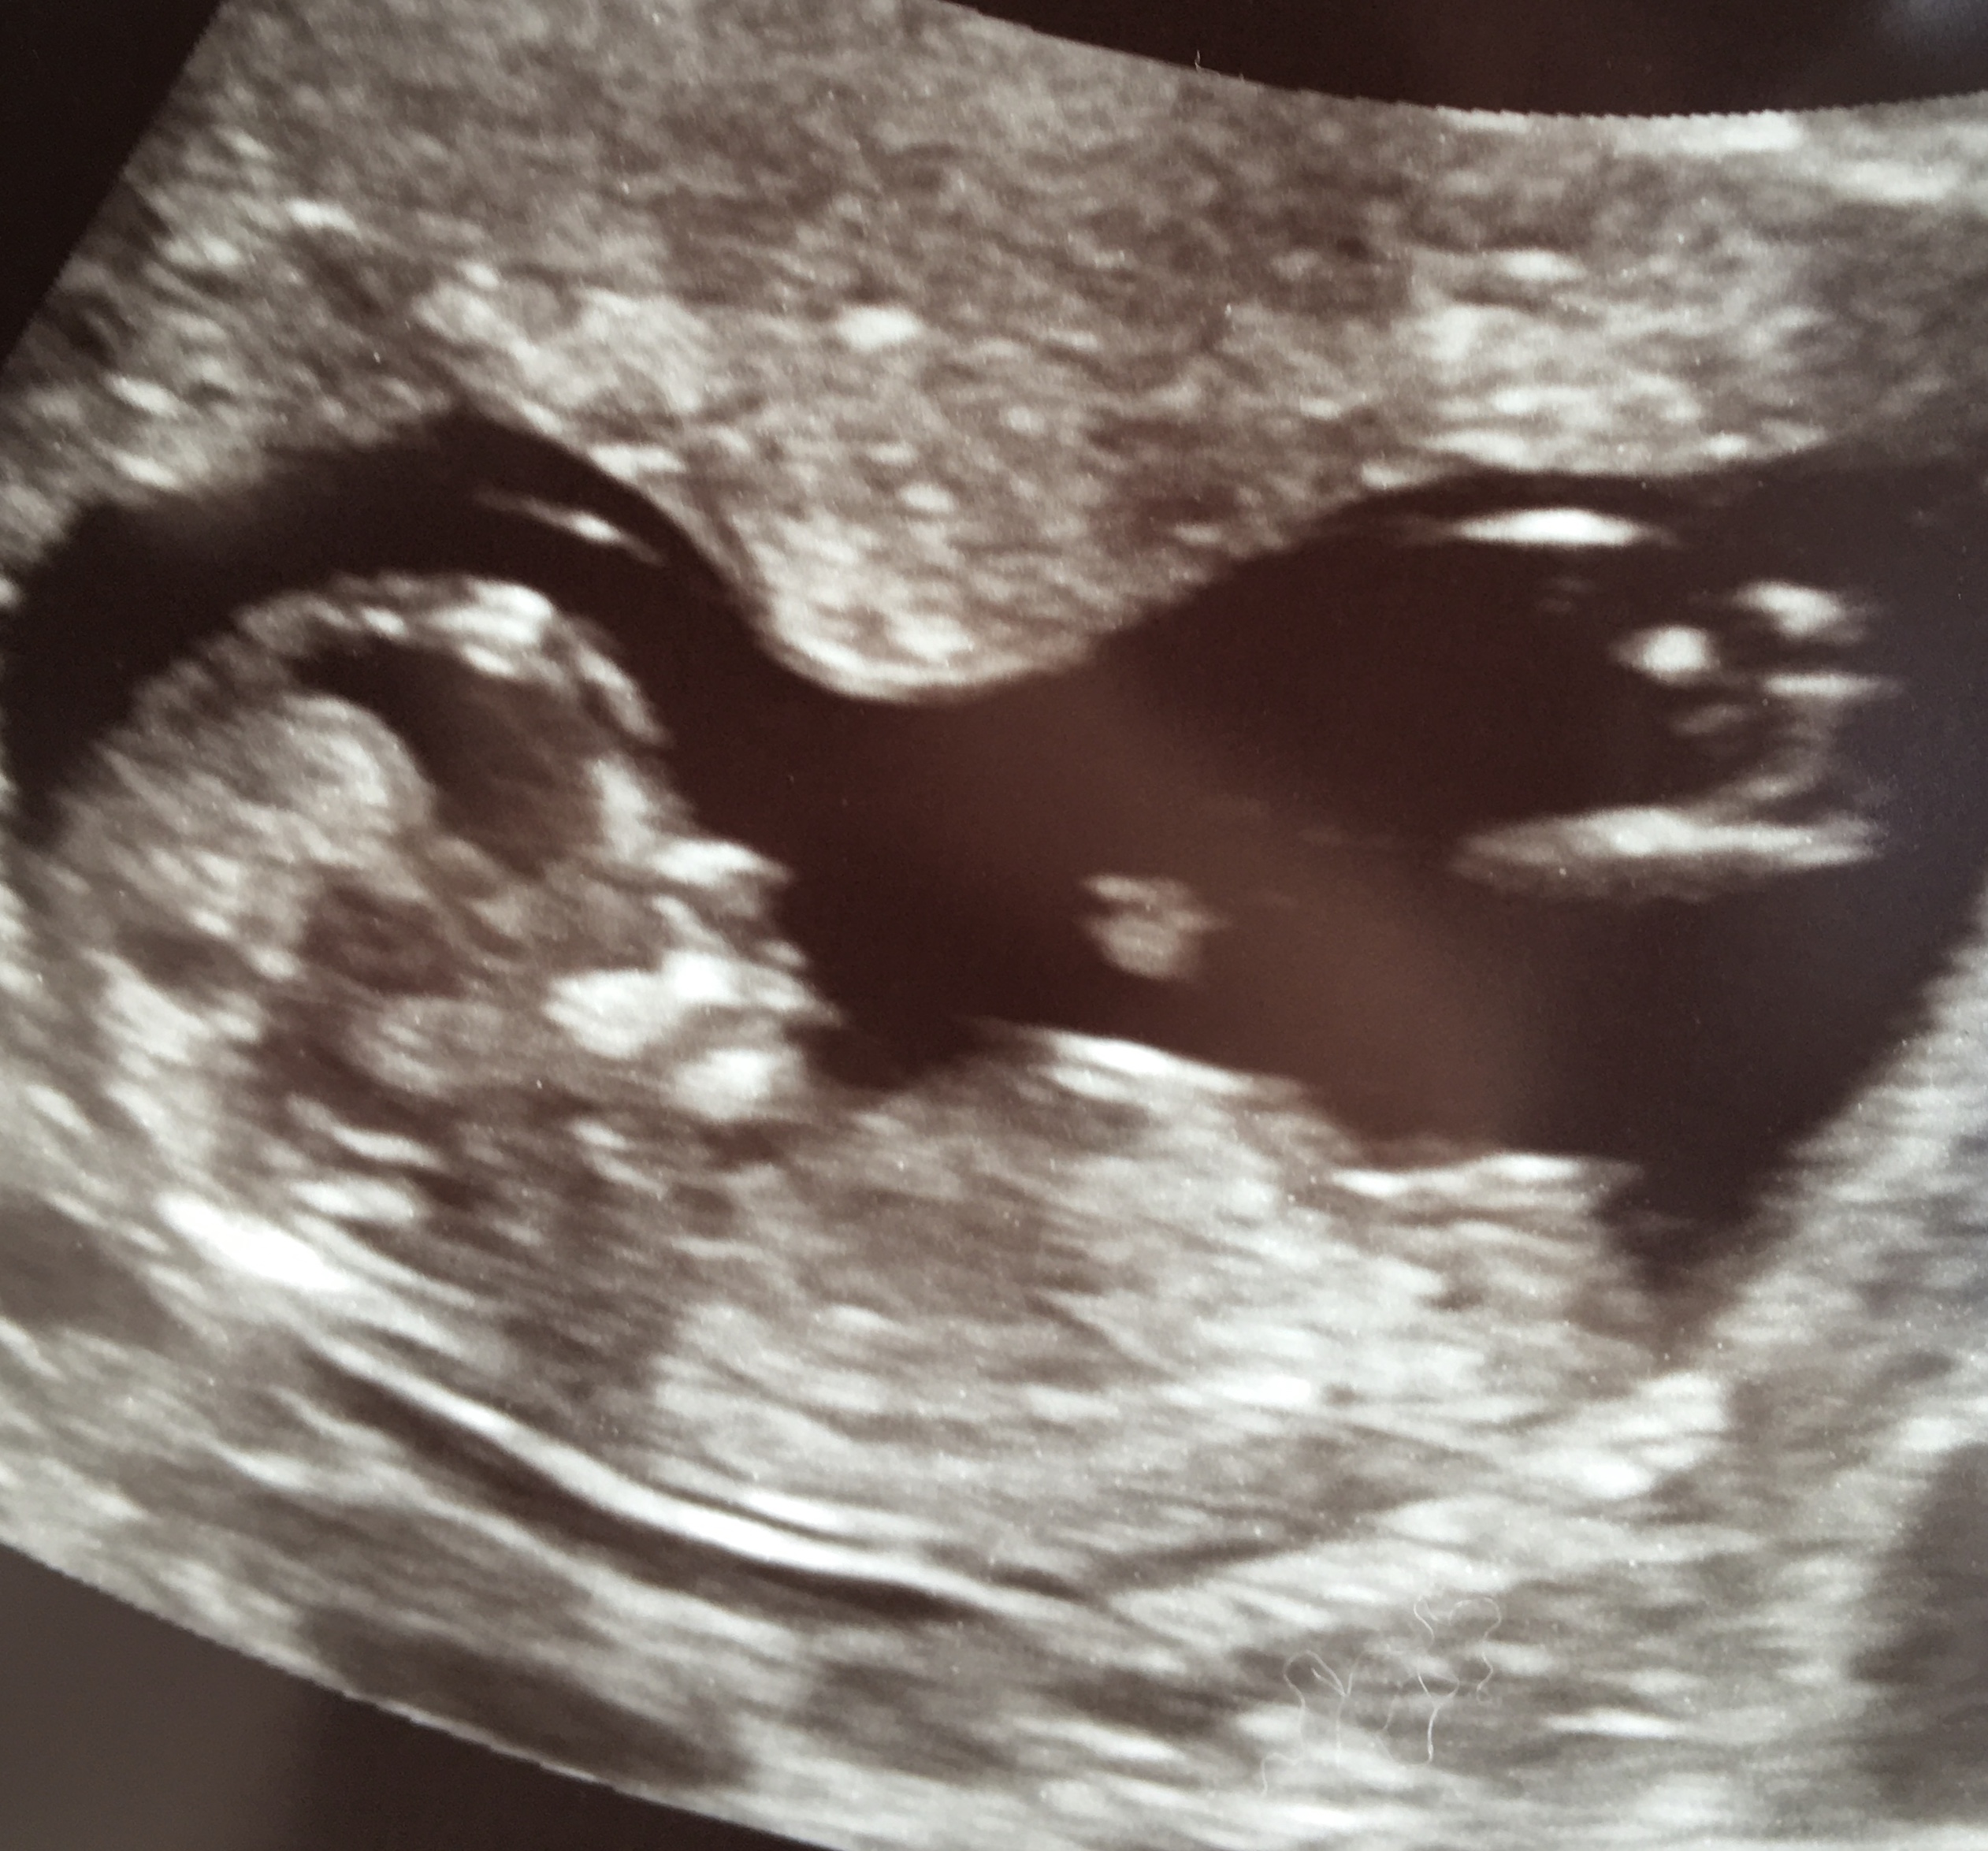

Confirmed Girl today at 16week gender US 😊🎀

Looks pretty flat to me I would be guessing girl!! Congratulations!

Girl- not expert but so much like my girls scan pics - the nub and position. Very girly [emoji4][emoji4]

Definitely a girl with that nub! Trust the nipt and go internet shopping!!!